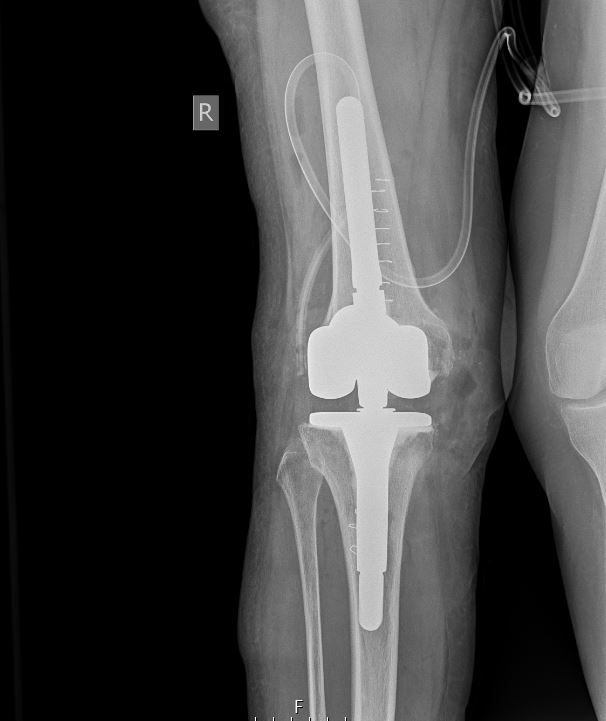

Ακτινολογικός έλεγχος: σε κάθε αναθεώρηση πρόθεσης οι απλές ακτινογραφίες είναι απαραίτητες καθώς μπορεί να απεικονίζονται ακτινοδιαυγαστικές γραμμές και περιοχές με απώλεια οστού.

Τα μεγαλύτερα προβλήματα που αντιμετωπίζει ο χειρουργός κατά την αναθεώρηση μιας χαλαρωμένης πρόθεσης του γόνατος είναι ο ουλώδης ιστός από την προηγούμενη επέμβαση και η οστική απώλεια. Με την ανάπτυξη προθέσεων διαφόρων σχεδιασμών ανάλογα με το είδος του αστικού ελλείμματος και με την βελτίωση της χειρουργικής τεχνικής, τα καλά αποτελέσματα υπερβαίνουν το 80 τοις 100 στη δεκαετή επιβίωση των ολικών αρθροπλαστικών.